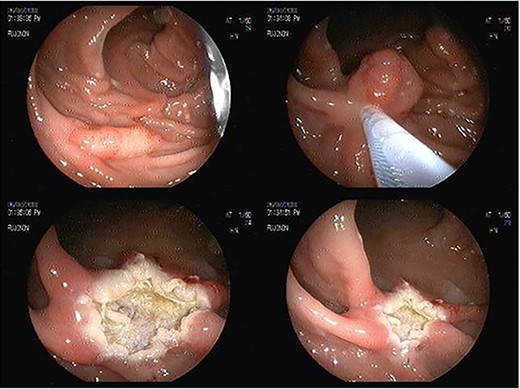

Analgesic management was prescribed, blood chemistry and thorax and abdomen X-ray were performed without abnormal results. An abdominal CT was performed, which showed concentric, focal thickening of the cecal walls, with a maximum thickness of 30 mm in the lateral wall, with enhancement with contrast, without evidence of pneumoperitoneum (Fig. 2). Given the history of recent polypectomy, patient’s symptoms, and the absence of signs of intestinal perforation, the diagnosis of PPS was made. Bowel rest, parenteral fluids and antibiotics (third-generation cephalosporin) were indicated, with a full recovery. The patient was discharged 24 h after admission. She was later evaluated in the coloproctology outpatient clinic, with complete resolution of symptoms. The histopathological study of the resected polyp was described as a hairy tubular adenoma. She was scheduled for a 1-year follow-up consult with a new colonoscopy study.

Abdominal tomography without pneumoperitoneum and with thickening of the concentric intestinal wall, without signs of intestinal perforation.